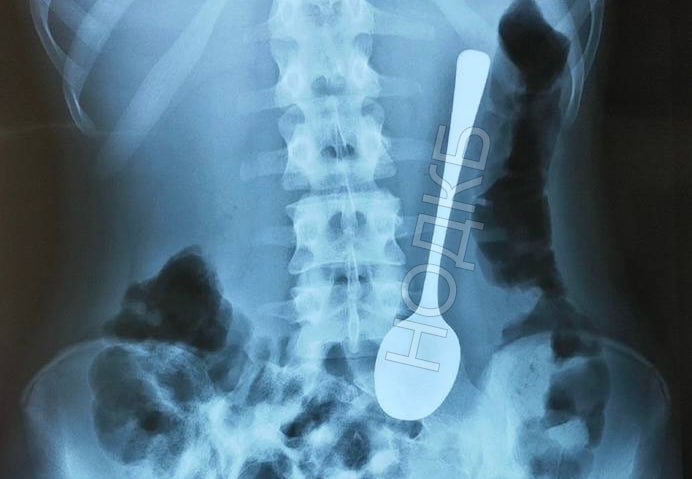

Нижегородский врач извлек ложку из желудка ребенка

Фото: телеграм-канал "Бокал прессека"

В Международный день врача-эндоскописта заведующий отделением НОДКБ Александр Дворянинов вспомнил, как однажды извлек проглоченную ребенком чайную ложку. О необычном случае написал Алексей Никонов в своем телеграм-канале "Бокал прессека".

По словам врача, все началось с неожиданного звонка от хирургов. Они сообщили, что в приемное отделение поступил юный нижегородец с десертной ложкой в желудке.

Операция прошла без наркоза. С помощью гастроскопа врачам удалось аккуратно достать инородный предмет.

Извлеченная ложка стала экспонатом музея инородных тел в НОДКБ.